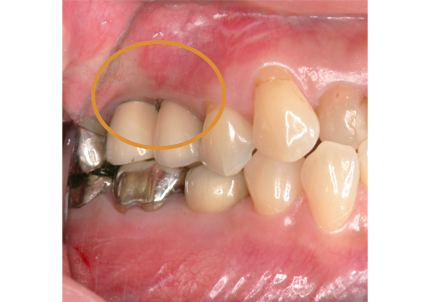

3.右上インプラント補綴物装着(2009年7月24日)

↑ 右上サイナスリフト後にインプラント埋入

4.左上下7番インプラント補綴物装着(2010年5月24日)

8.初診より現在に至る

強い歯ぎしり、くいしばりで奥歯の歯牙破折、深い虫歯で保存不可能となり全顎治療となる。

↑ 2007年6月30日(初診)

↑ 2025年9月9日

治療後は経過良好